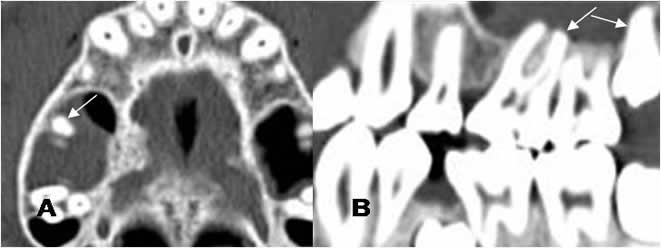

Fig 38. Enfermedad endodental.

A: TAC axial, B: TAC reconstrucción coronal y C: TAC reconstrucción sagital.

Reemplazo de la pulpa de los dientes, por caries extendidas internamente. (Flechas gruesas). Se encuentra perilucencia periapical, por enfermedad endodental.(Flechas delgadas).